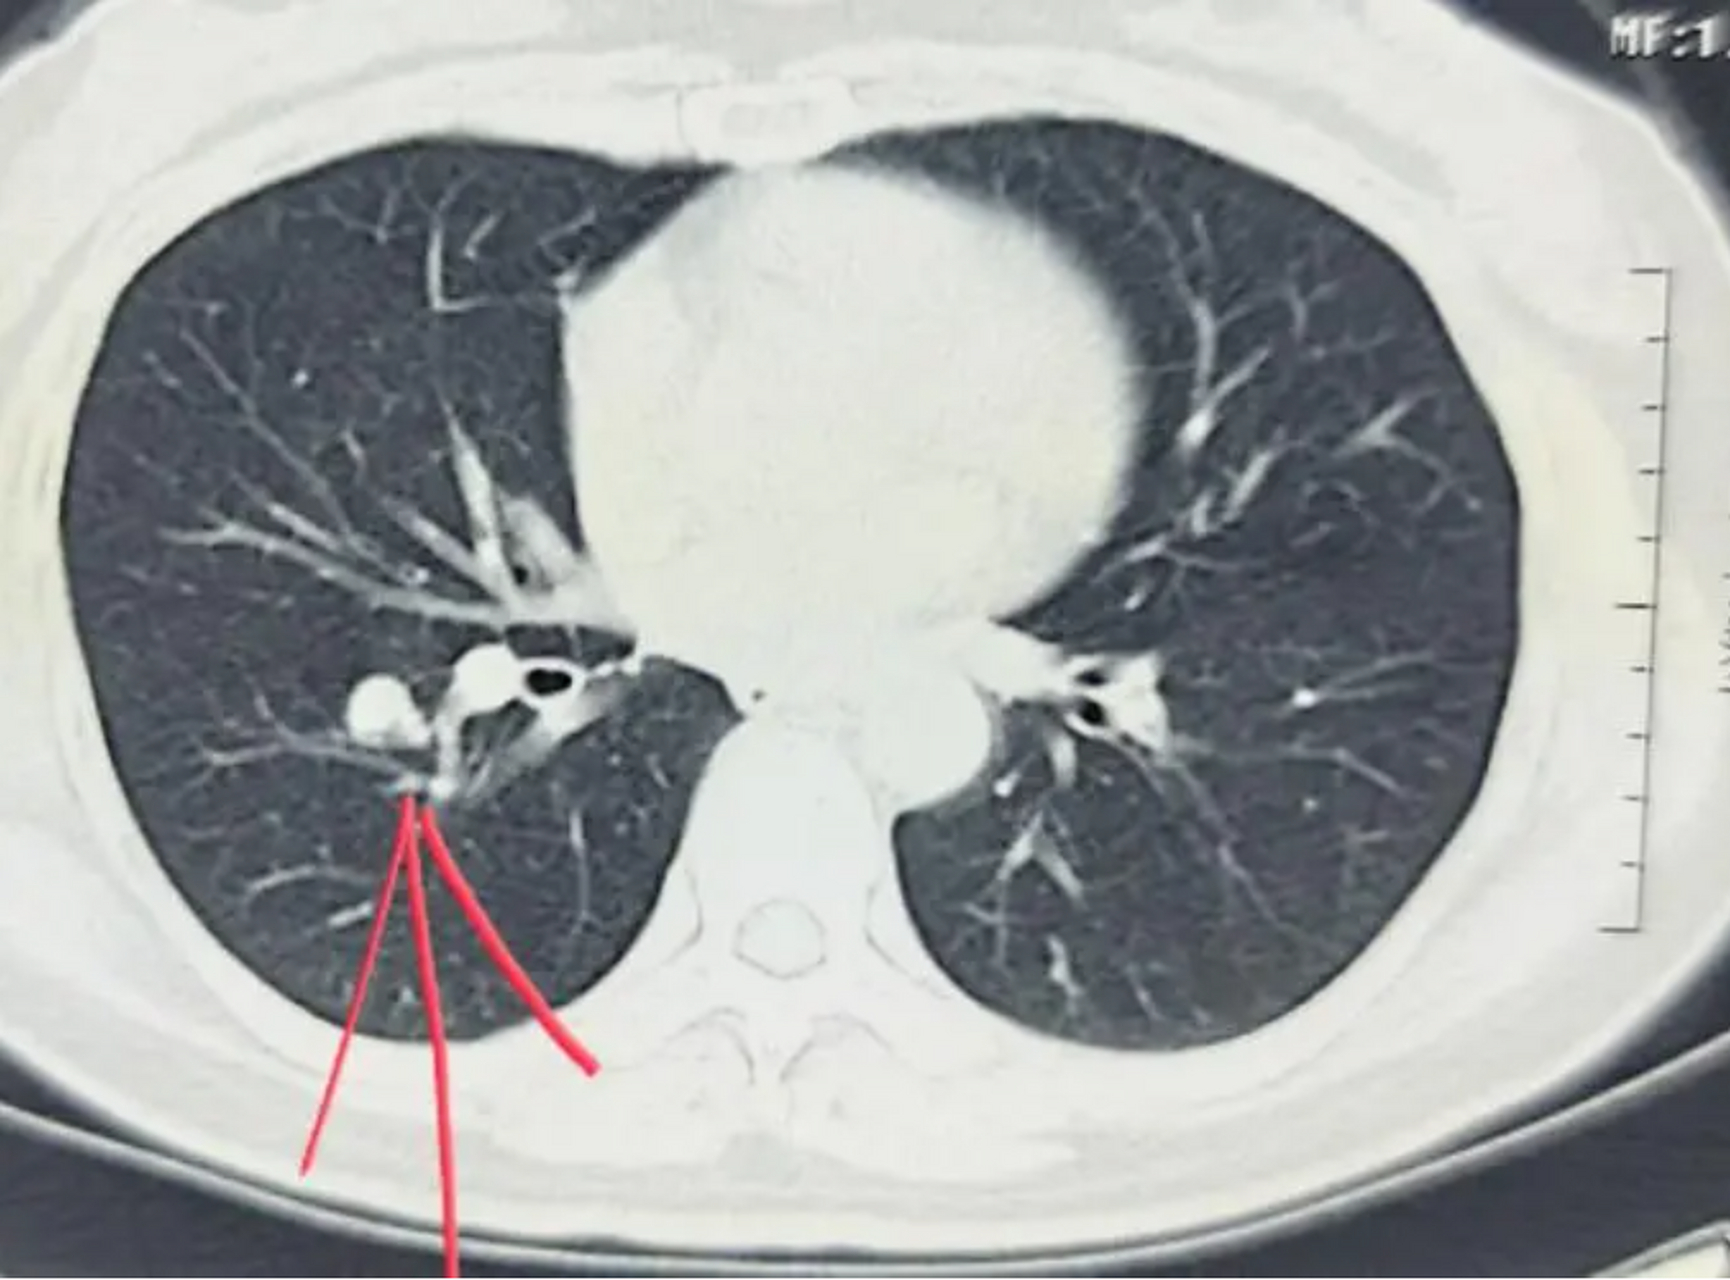

11个肺ct报告的潜台词,看一遍就能懂 1,纤维灶:一般指良性病变,指曾经

图片尺寸1730x1280